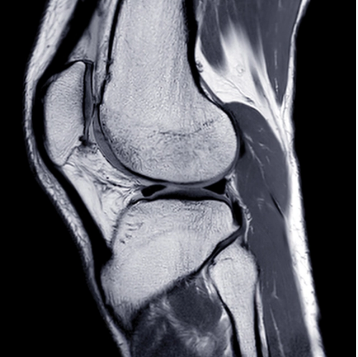

This online CME course delivers a comprehensive state-of-the-art update on clinically relevant topics in neuroradiology and musculoskeletal imaging, including a discussion of optimized protocols with 1.5T and 3T MR. Faculty review indications commonly seen in general practice, along with updates designed to improve image acquisition and interpretation strategies.

- Major joints

- Recognize internal derangement and post-operative appearances of the shoulder, elbow, wrist, hip, knee, ankle and foot

- Knee Menisci – Pearls and Pitfalls – Lynne S. Steinbach, MD